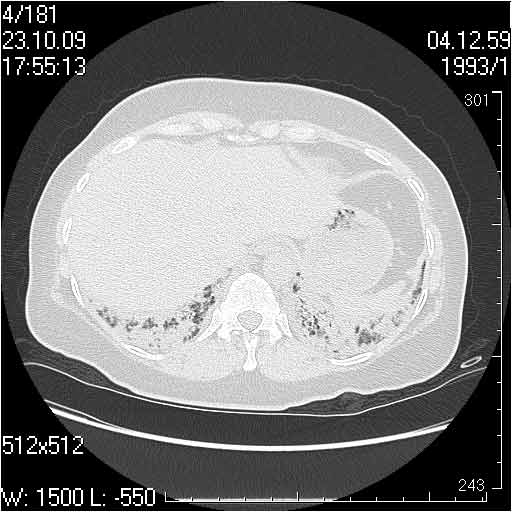

Случай №2

Мужчина 54 лет

Случай 2: картина патологических изменения довольно типична: GGOs & thickened interlobular septas = "crazy paving" sign. Наличие плотностей по типу матового стекла в сочетании с утолщением междолевых перегородок, даёт признак булыжной мостовой; на первом месте будет стоят диагноз альвеолярных протеиноз.